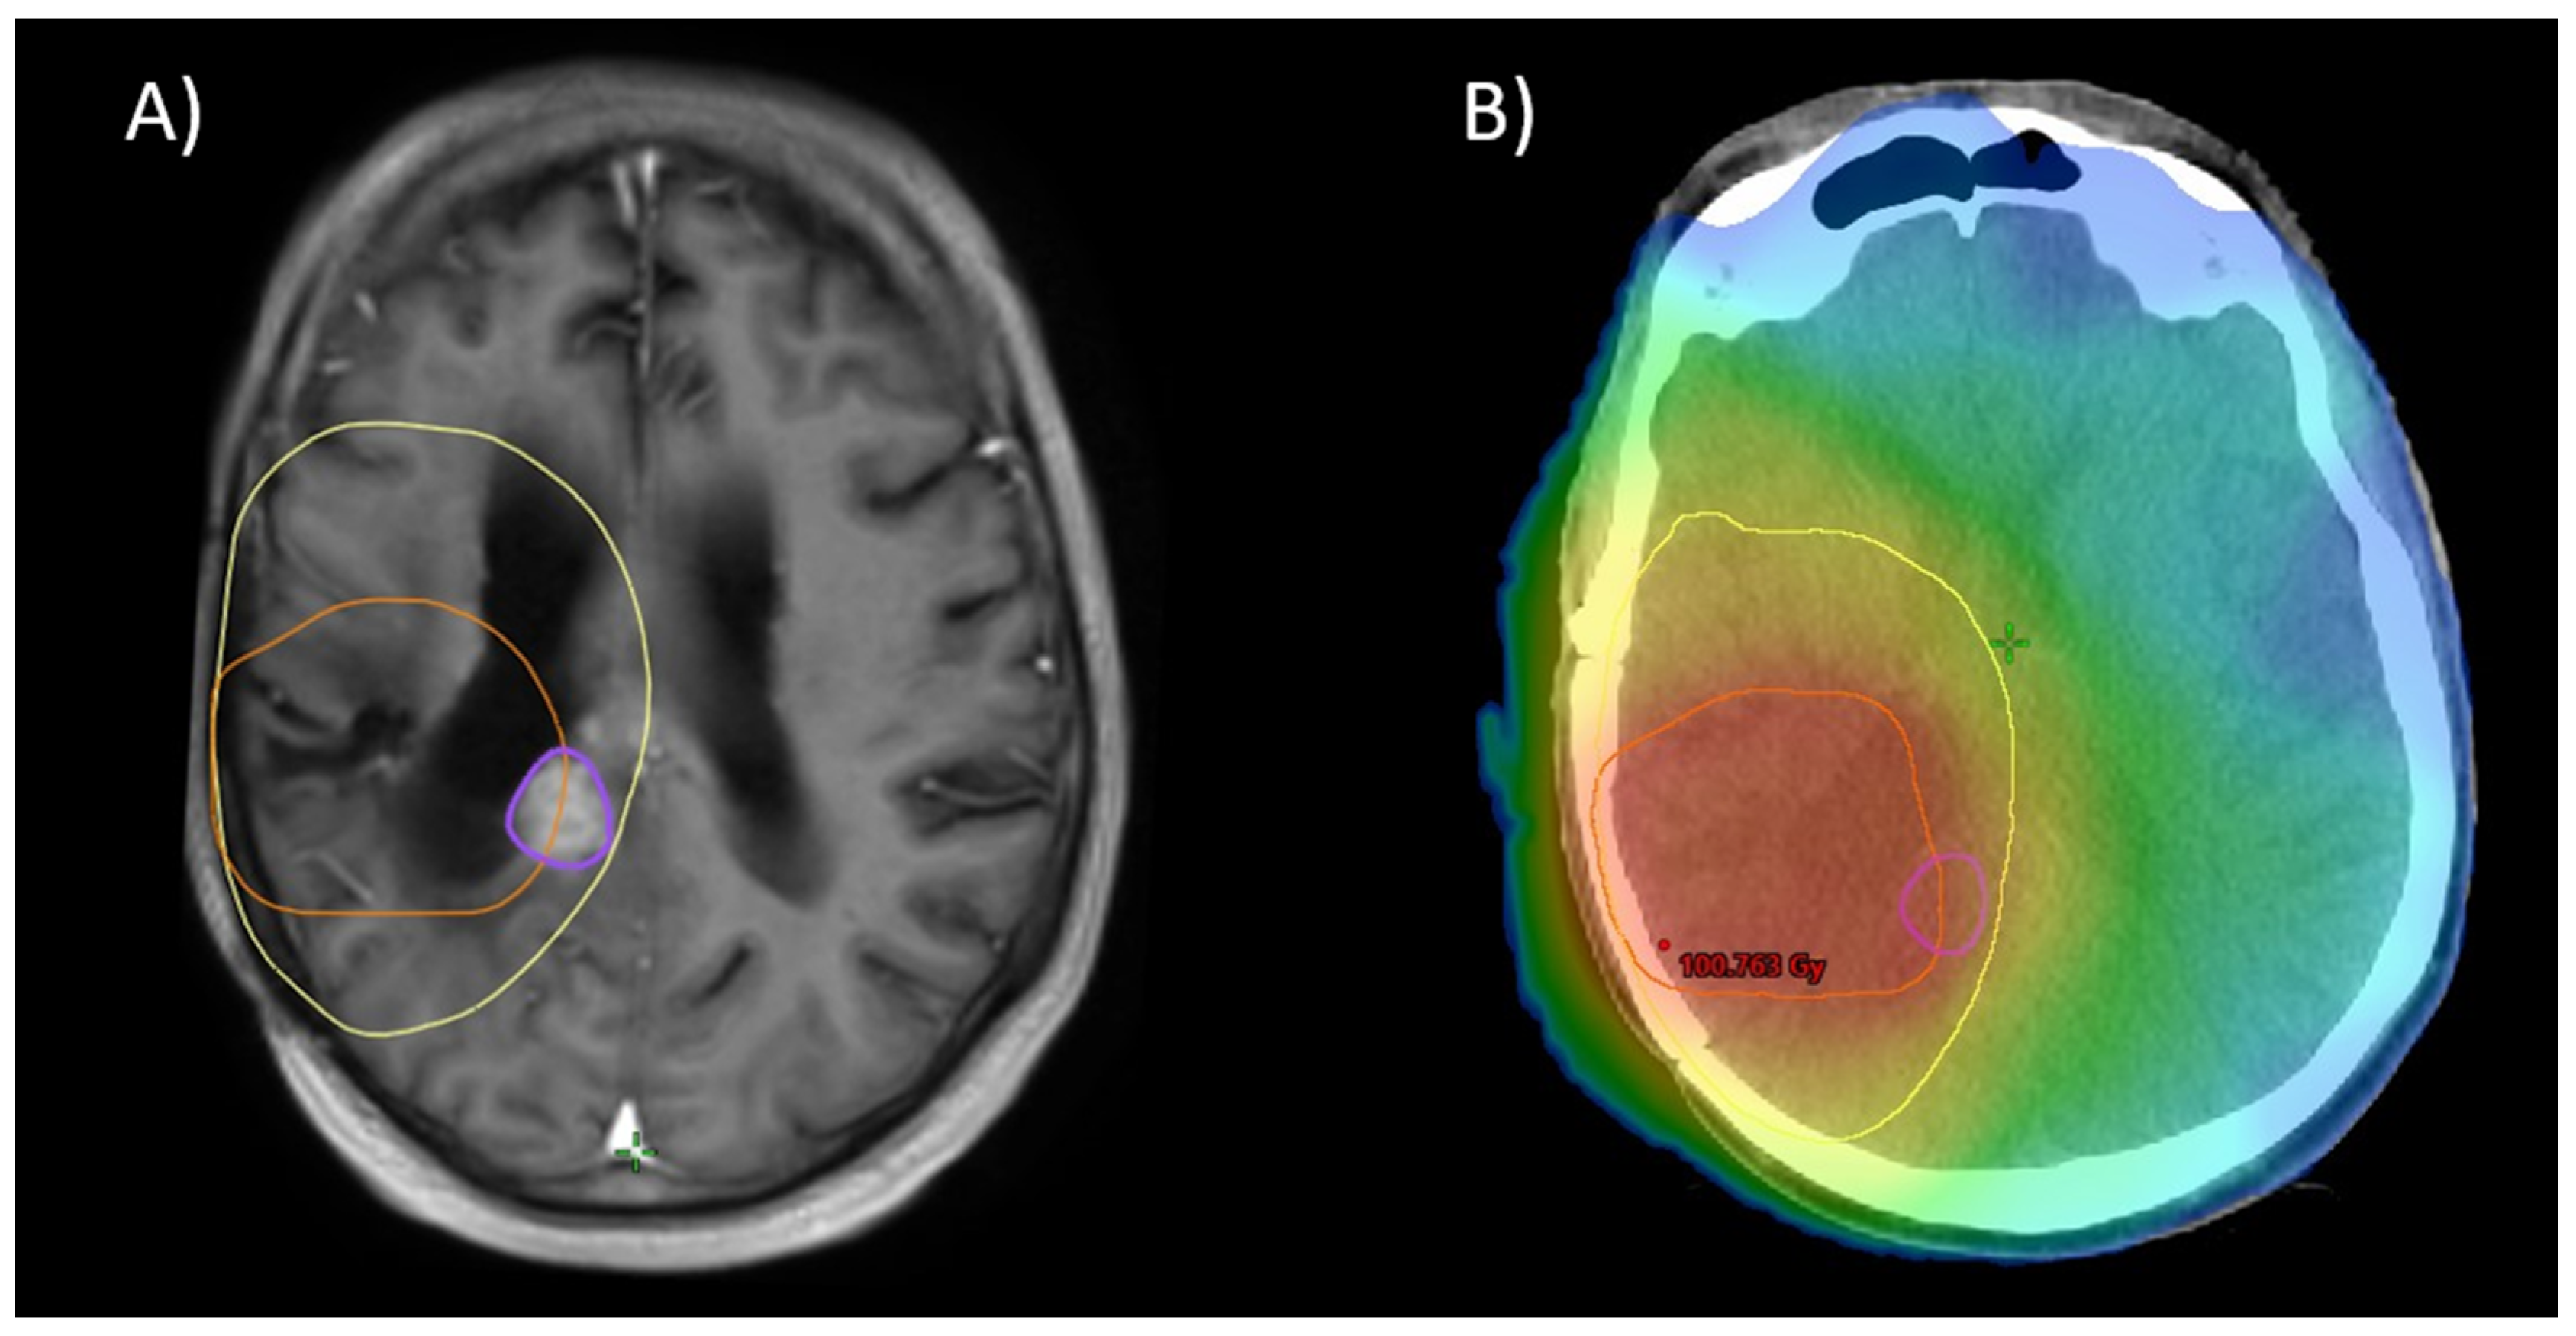

- Chemoradiotherapy